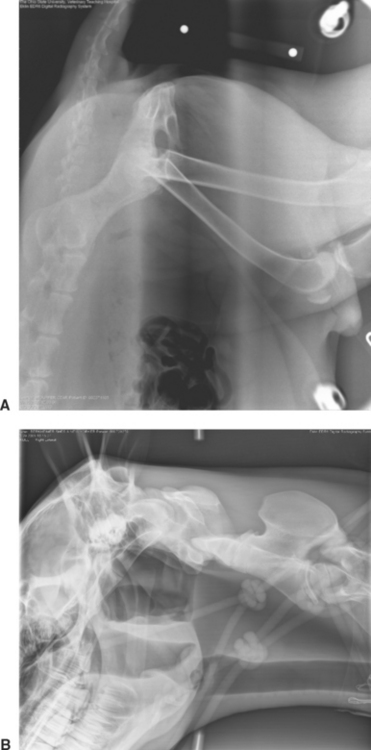

A number of operator-dependent imaging processing procedures can create artifacts if not applied properly. An example of this is a commonly encountered radiolucent “halo” around metallic orthopedic implants that can mimic implant infection and loosening. This is termed the Uberschwinger or rebound effect and occurs when the density of adjacent objects is significantly different (Figs. 22-11 and 22-12). Another example is a thoracic radiograph with extreme contrast that mimics lung pathology due to exaggerated edge enhancement (Fig. 22-13). Image processing parameters and application are CR manufacturer dependent. Image processing is a specific area of training that users of a new CR system should embrace.

Figure 22-16 Severe overexposure has caused the trachea, endotracheal tube, portions of the hyoid bone, and the cervical soft tissues to “fade away” and become black in this lateral cervical image taken during myelography. A black “halo” also exists around the periphery of the dog where the skin is “burned out.” This degree of overexposure cannot be corrected at the digital workstation, and the exposure must be repeated. These errors should rarely, if ever, occur once a digital technique chart has been established.